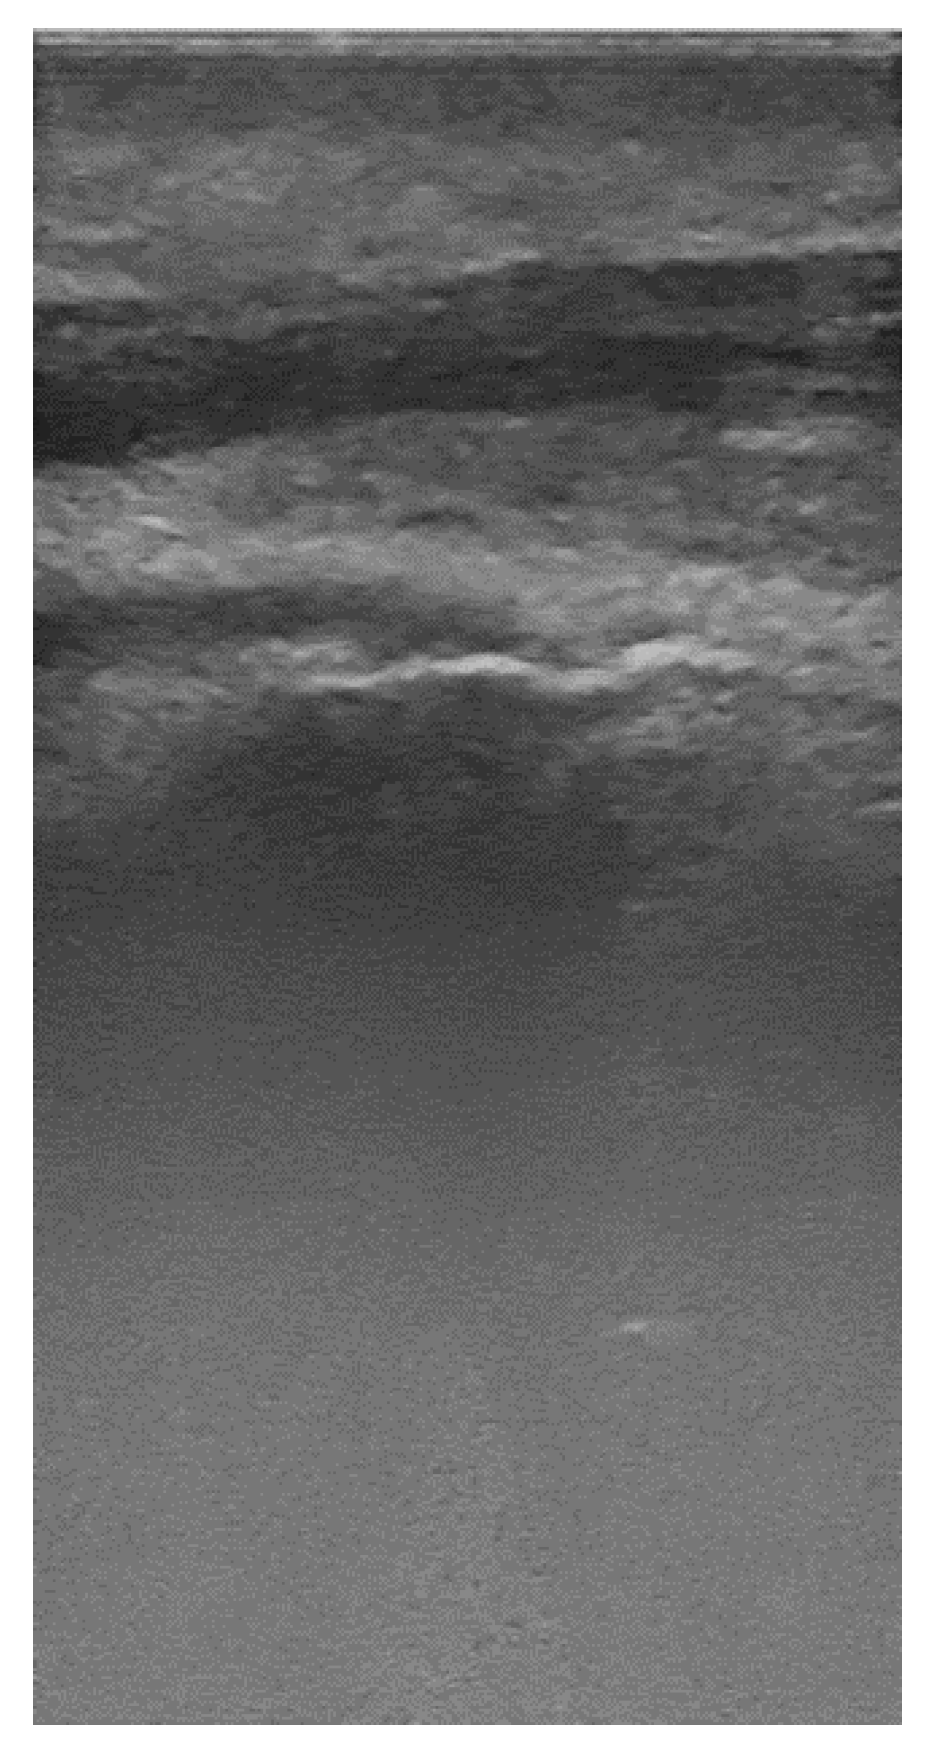

- Cropping the images and the mask to the size compatible with Mask R-CNN. Considering that the ultrasound images and the masks have 375 × 735 pixels and that the lower half part of the images do not contain useful information, the images and masks were cropped in a vertical direction and extended in a horizontal direction to a dimension of 384 × 384 pixels.